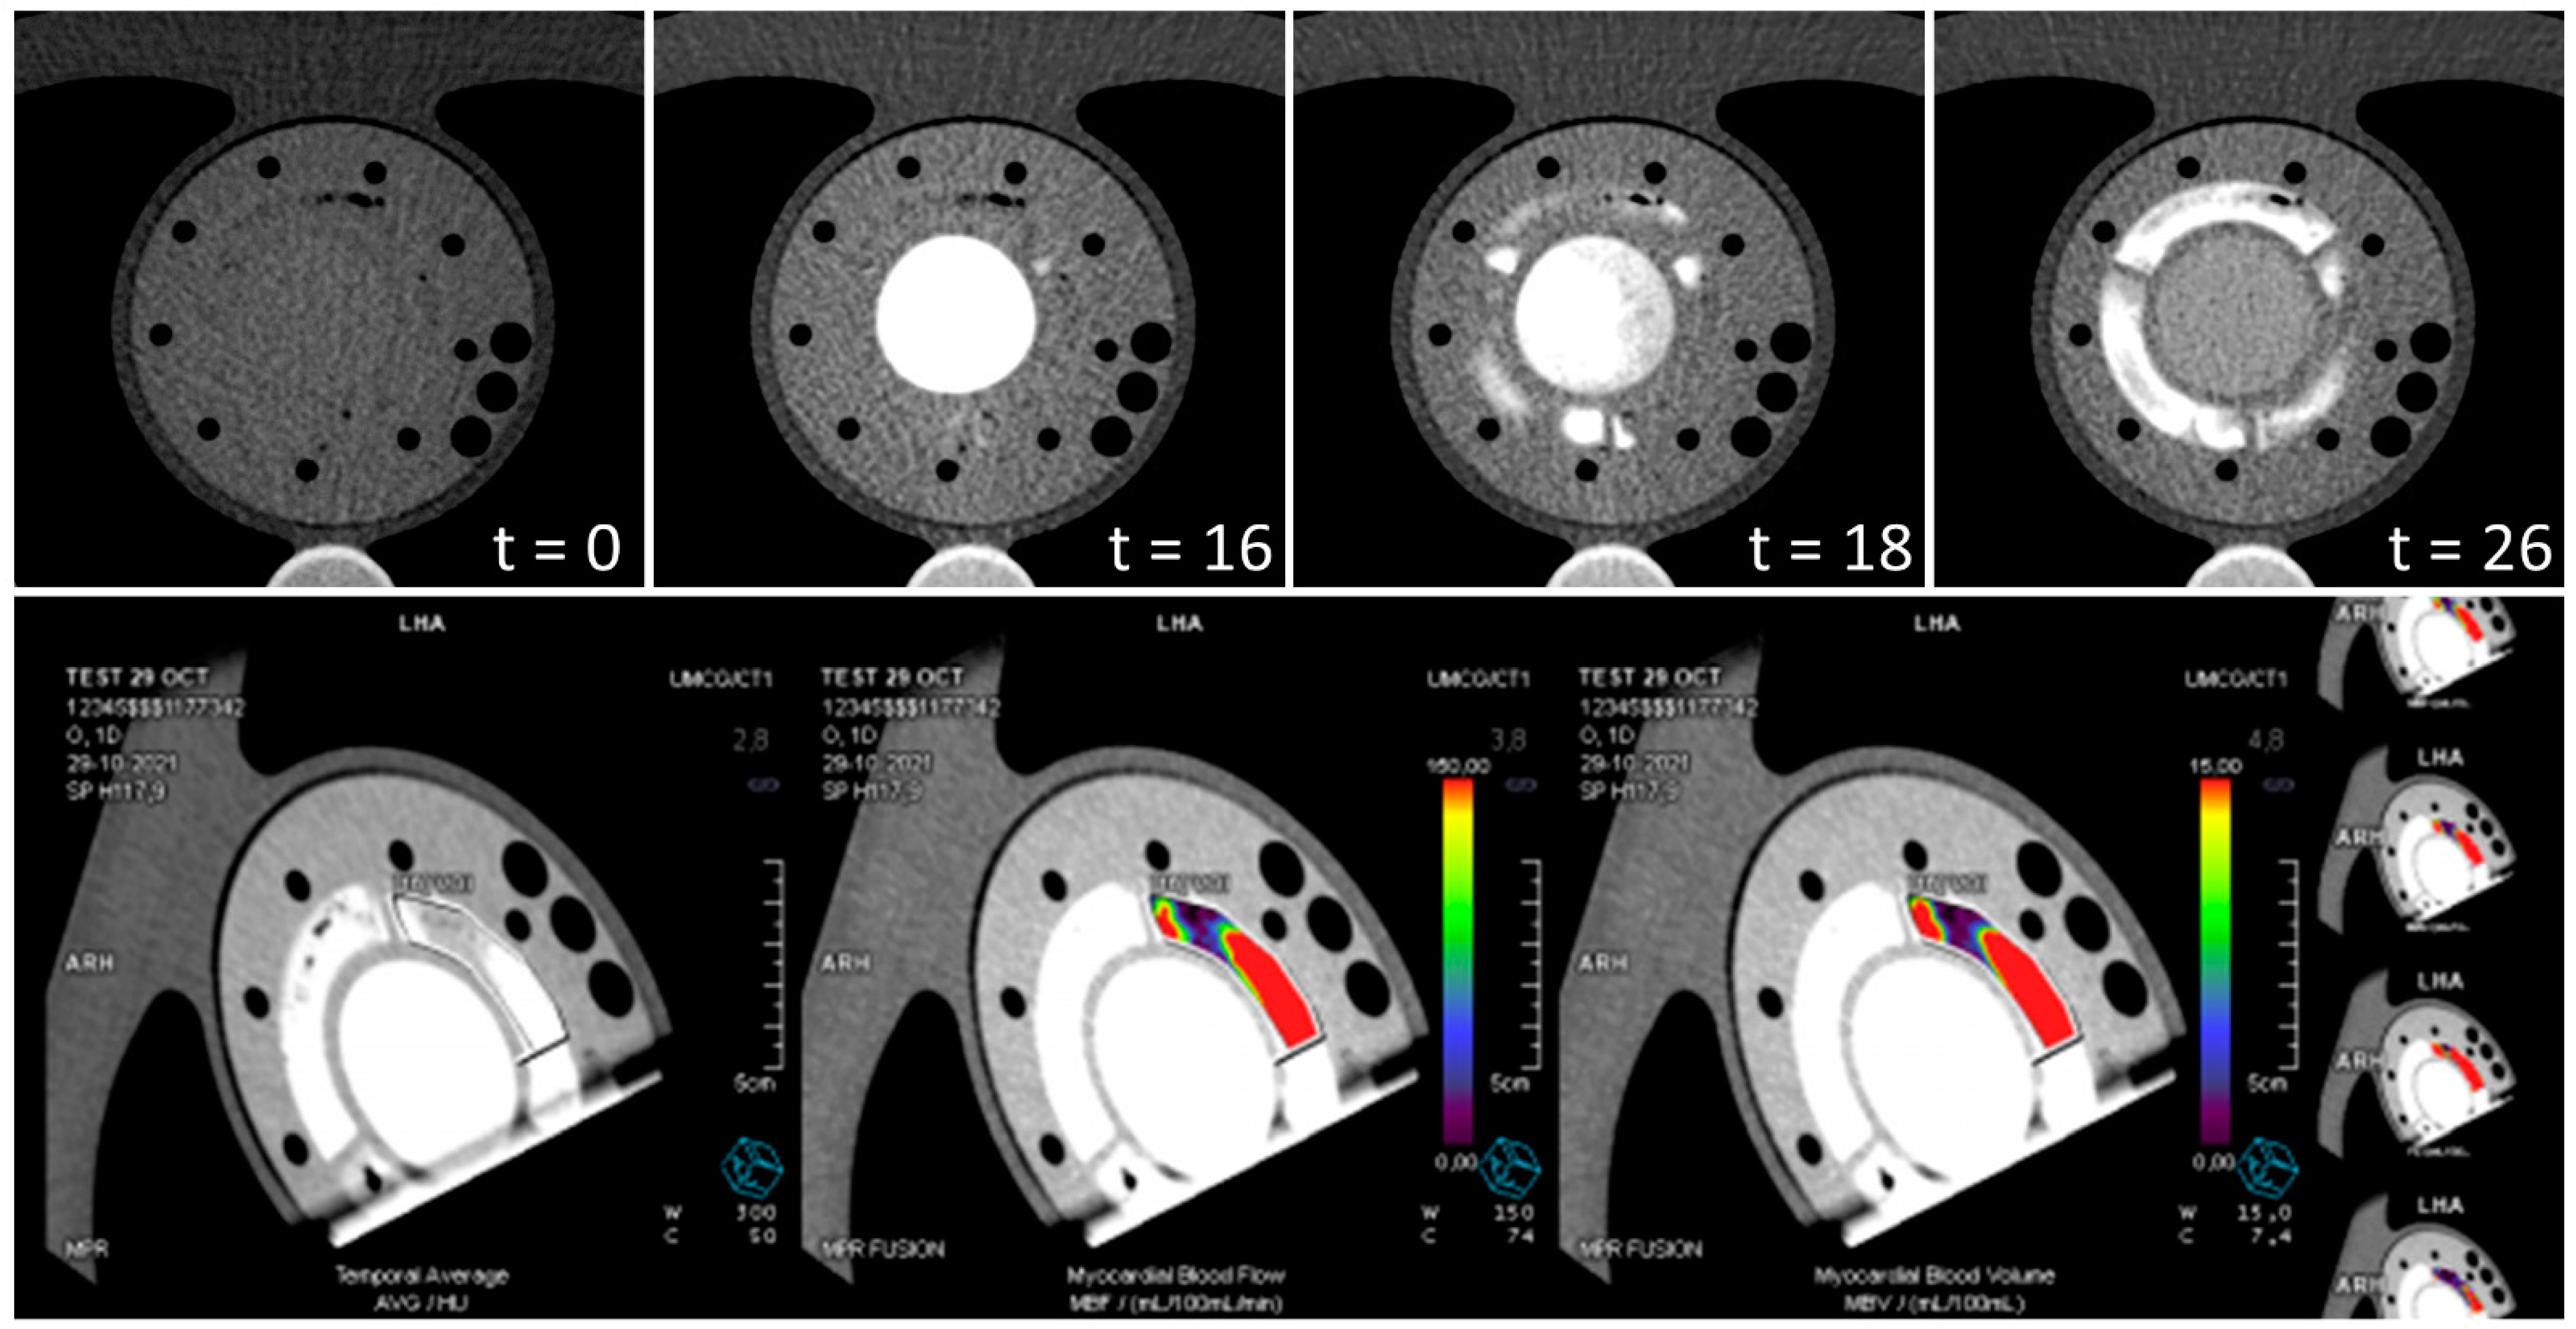

Figure 4 illustrates clinical analysis of two dynamic PET-MPI data sets. The use of different tissue mimicking material compositions resulted in varying tracer uptake as shown in the uptake polar maps. The tissue region depicted by heart segment 9 showed the highest tracer uptake level, corresponding to myo2 in the phantom. Tracer uptake was almost absent in segment 11, which matched myo3. The second row in Figure 1 plots a repeated phantom measurement with background subtraction of previously accumulated radiotracer. Scan 1 and 2 showed a similar relative tracer uptake distribution across the mimicked myocardial tissue, though deviated from each other in terms of absolute computed MBF values. Figure 5 demonstrates myocardial perfusion image visualization and analysis in CT. The top row illustrates a phantom image time-lapse across the short axis showing contrast arrival and distribution within the LVC and myocardial regions. A perfusion deficit was simulated in the rightmost tissue region. Figure 5 displays typical MBF analysis of a VOI in consecutive image slices. An example dynamic phantom image series obtained with MRI is visualized in the top row of Figure 6. Underneath a typical (partial) software display is presented for subsequent perfusion analysis.

The phantom setup used was not dedicated for measurements with CT; hence, we performed a measurement series upfront for optimization purposes. With minimal adjustments to phantom and flow circuit design, it became possible to perform dynamic perfusion image acquisition using a slightly modified clinical protocol (see Video, Supplemental Digital Content S2). We performed initial perfusion analyses using associated clinical software. Remarkably, the mapped intensity profiles within the mimicked myocardium were higher compared to patient data [28]. This may be due to the made simplifications in phantom design in mimicking the pericardium and myocardium as one. In future research more suitable tissue-mimicking materials will be explored. Possibly this simplified anatomical representation also limits automatic delineation of the heart contours. Fortunately, we could manually delineate VOIs instead, though this type of evaluation is less easy to standardize for future research purposes and therefore less desirable for phantom validation purposes. MBF was subsequently calculated based on the average TICs within these VOIs. These values do not yet correspond to the reference values (Table 2) but do demonstrate the potential of future phantom applications.

This study has a few limitations. Only a limited number of measurements were performed per imaging modality (n = 3), which is sufficient for a first feasibility check, though requires more extensive research to draw up an adequate set of requirements for multimodal phantom (re)design. In line with this, for a complete multimodal phantom design it is also important to consider the differences between scanner types and manufacturers as well as clinical perfusion analysis software packages. In addition, better venting capabilities should be incorporated in the phantom design to diminish the presence of air bubbles. For example, small air bubbles were present during phantom measurements in CT, as depicted in the top myocardial region of the image time-lapse in Figure 5. Finally, this phantom feasibility study does not yet include quantitative MPI with contrast enhanced echocardiography. The materials used in current phantom model are not suited for use with ultrasound.

Figure 5. Example of CT myocardial perfusion image analysis. (Top) visualization of a time-lapse across a short axis plane of the phantom showing contrast arrival and distribution in the mimicked left ventricular cavity (center) and three surrounding myocardial regions (t = 0 s, 16 s, 18 s, 26 s). The rightmost tissue region simulates a perfusion deficit (flow of 40 mL/min instead of 80 mL/min). (Bottom) a typical software display of CT myocardial perfusion image analysis in consecutive image slices. The level of estimated myocardial blood flow within the manually delineated volume of interest is visualized by the added color and ranges from 0 (purple) to 150 mL/100 mL/min (red).